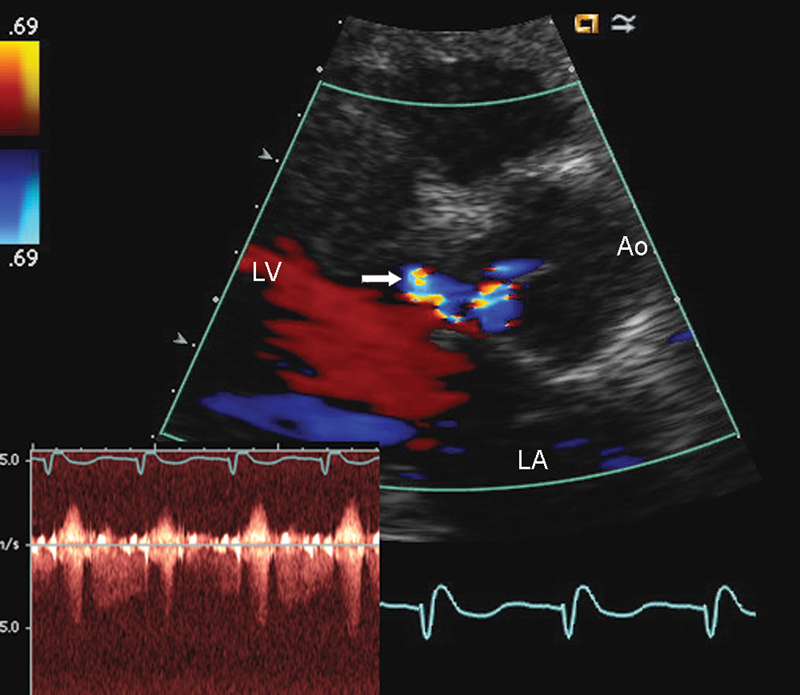

فحوصات تشخيصية لبعض امراض القلب والشرايين التاجية